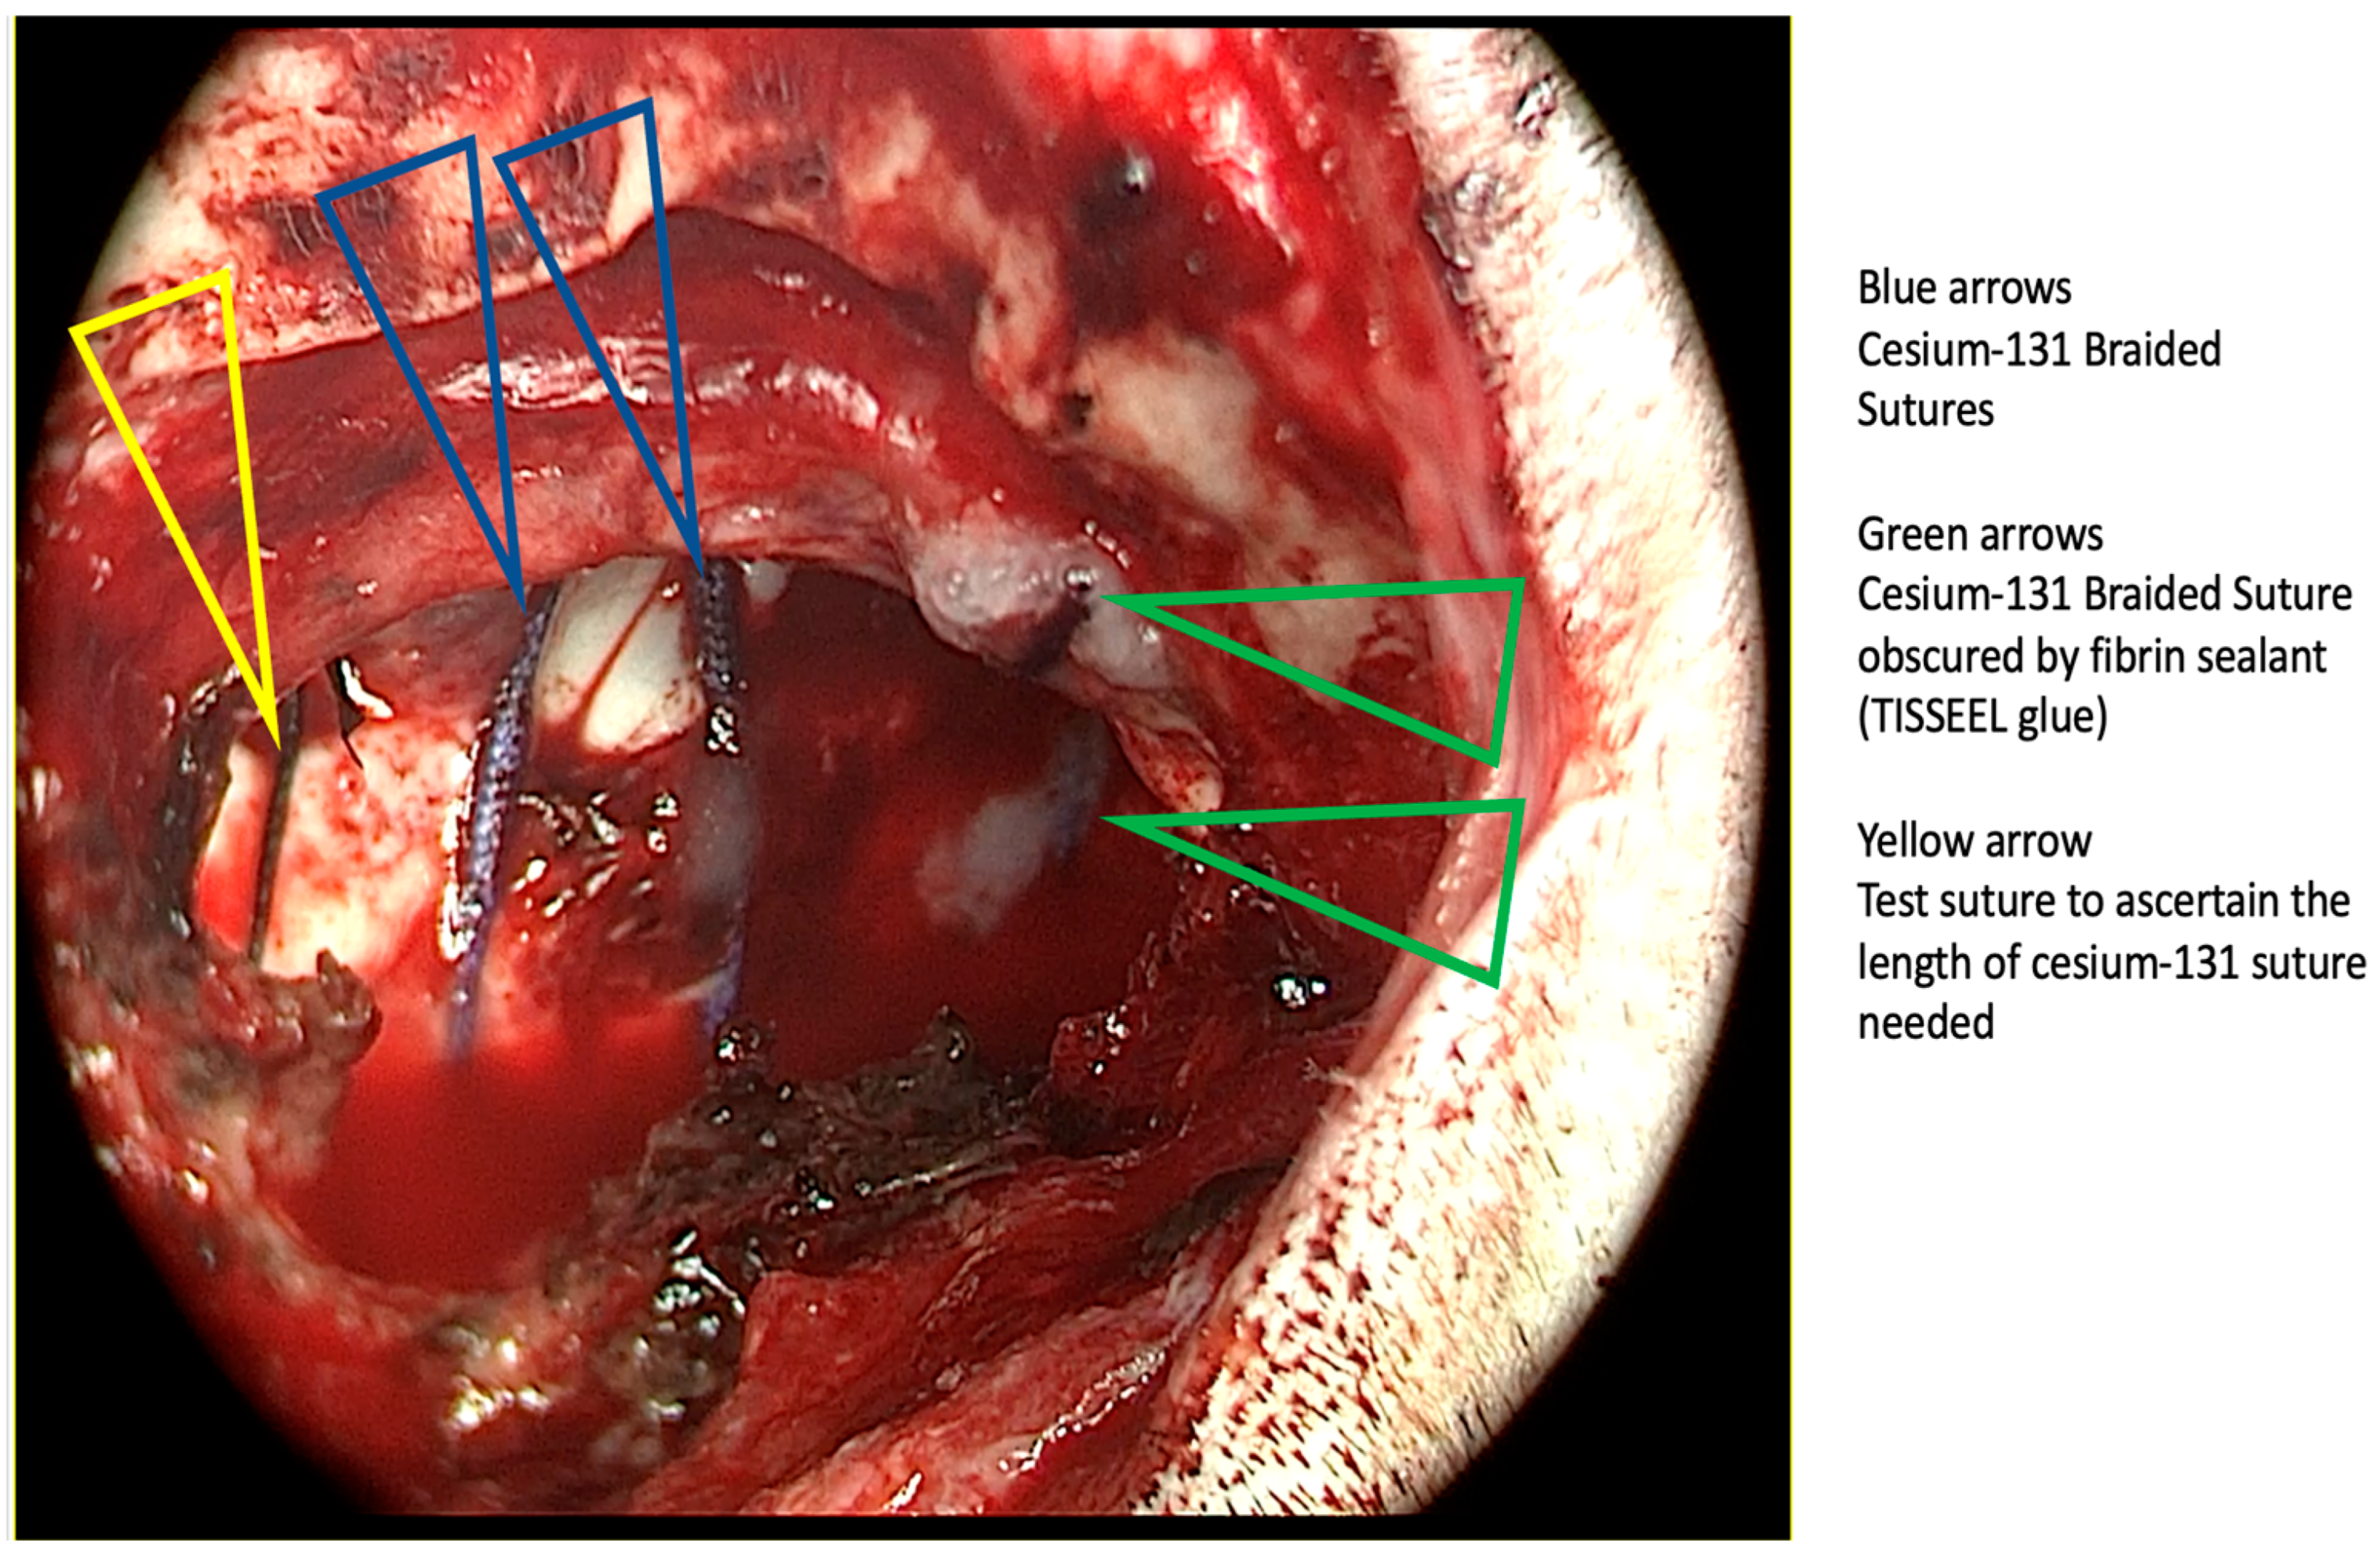

3.2. Cesium Brachytherapy